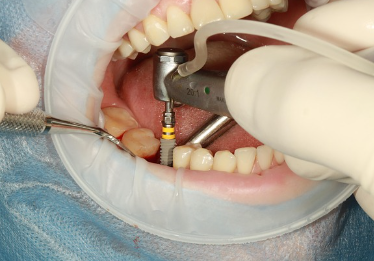

임플란트란 무엇인가요?

임플란트란 치아가 빠졌을 때 인공치근(임플란트)을 잇몸 뼈에 식립해 자연치아처럼 기능하게 만드는 치료입니다.

자연치에 가까운 기능과 외관을 제공하기 때문에 많은 분들이 임플란트를 선택하고 있습니다.